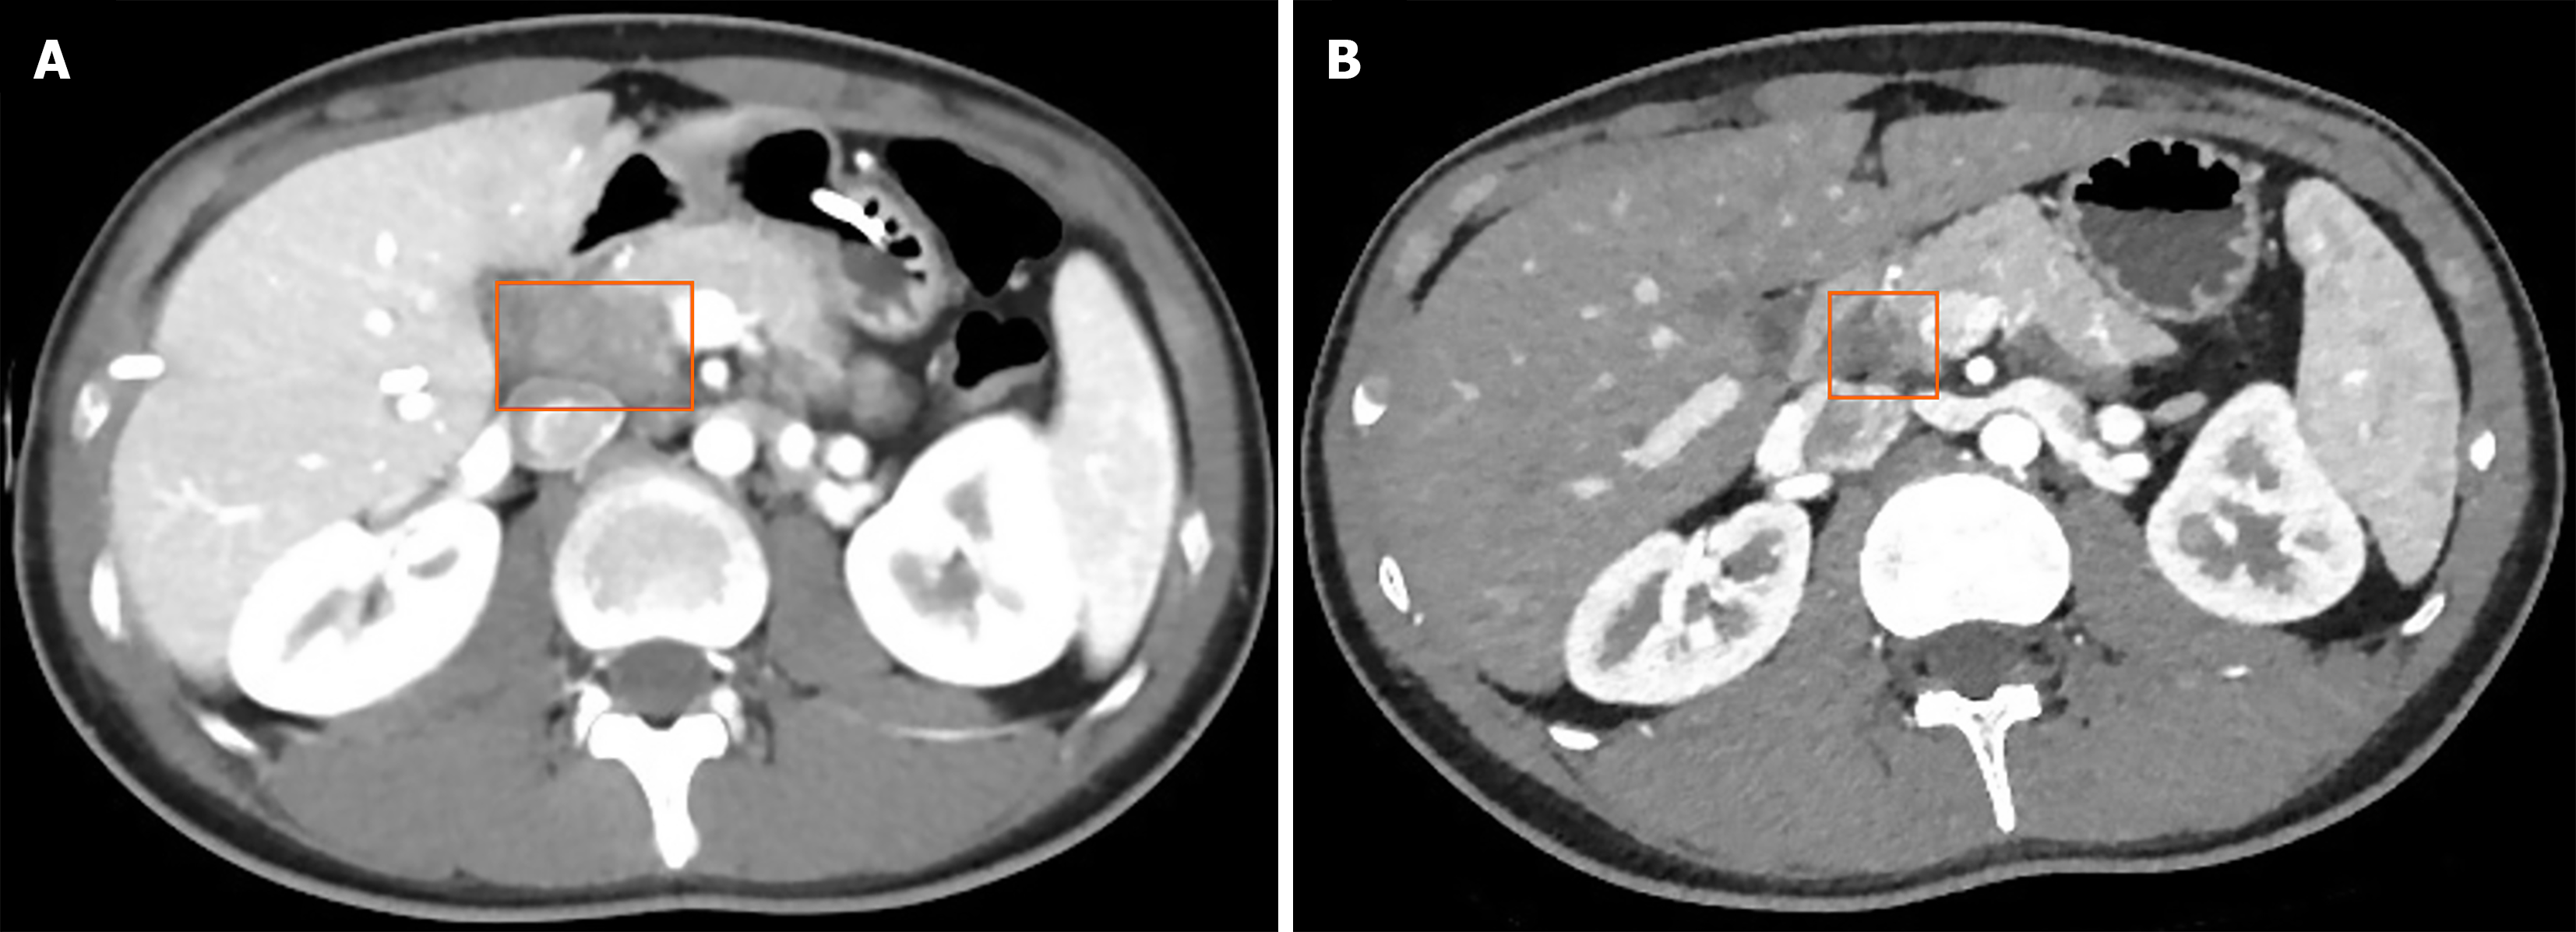

Figure 1 Abdominal contrast-enhanced computed tomography images.

A: An irregular hypodense mass located in the duodenum and pancreatic head, measuring approximately 29.8 mm × 22.0 mm (orange box), with multiple internal air-fluid levels. The mass demonstrates peripheral contrast enhancement and indistinct surrounding fat planes, indicating local inflammatory infiltration or possible extension; B: Follow-up imaging shows a mildly hypodense mass in the duodenal-pancreatic head region, reduced in size compared to the prior scan (December 25, 2023). Previously observed gas and fluid components have been absorbed (orange box).